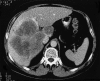

Objective: To describe the surgical techniques and early results of inferior vena cava (IVC) resection in patients with advanced liver tumors.

Summary background data: Involvement of the IVC by hepatic tumors, although rare, is considered inoperable by standard resection techniques. Concomitant hepatic and IVC resection is required to achieve adequate tumor clearance.

Methods: Between February 1995 and February 1999, 158 patients underwent hepatic resection for colorectal metastases in the authors' unit. Eight patients, aged 42 to 80 years (mean 62 years), with hepatic metastases from colorectal cancer underwent concomitant resection of the IVC and four to six hepatic segments. Resections were carried out under total hepatic vascular exclusion in four patients and ex vivo in four patients. Between 30 degrees and 360 degrees of the retrohepatic IVC was resected and replaced with an autogenous vein patch (n = 1), a ringed Gore-Tex tube graft (n = 2), a Dacron tube graft (n = 1), or a patch (n = 3) or was repaired by primary suturing (n = 1).